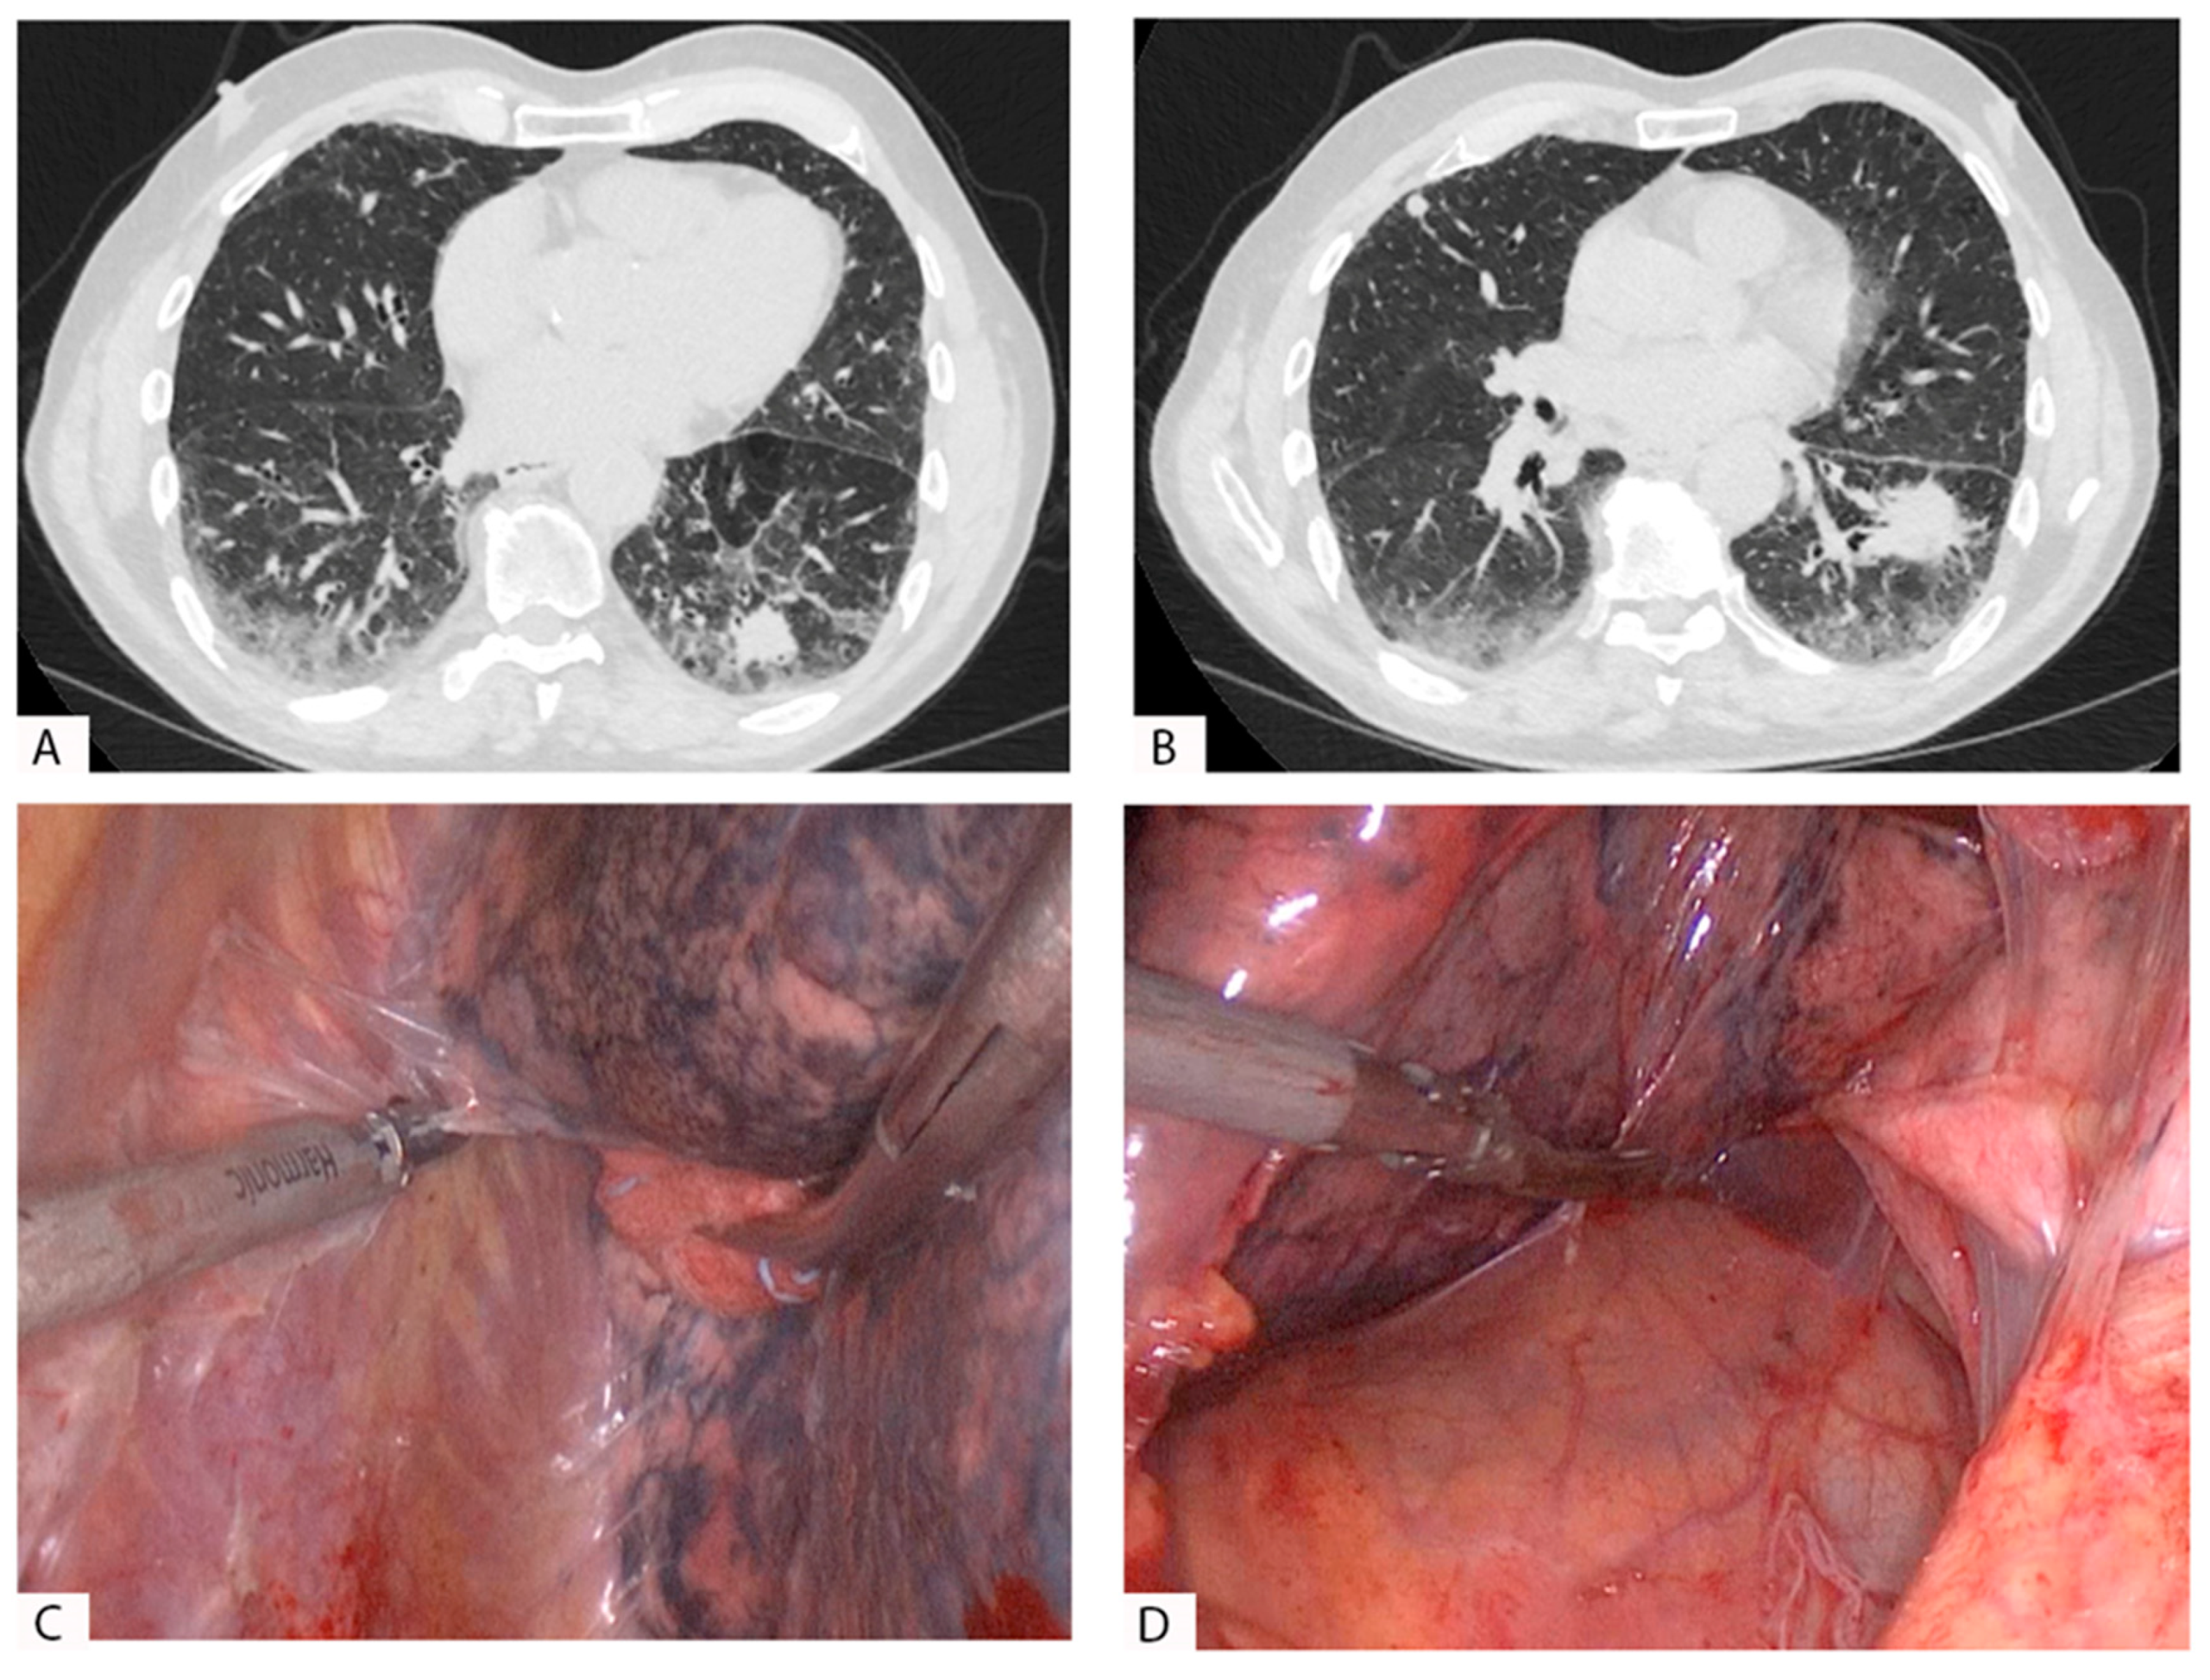

We reported two cases of extensive pleural adhesions in patients with a history of COVID-19 in Figure 1 and Figure 2; in both cases, the surgery was carried out using a thoracoscopy.

Figure 1.

A patient with two localizations of adenocarcinoma in the left lower lobe (LLL) treated with VATS lobectomy. The patient had COVID-19 with mild symptoms 80 days before surgery. (A,B): Post-COVID HRCT of the thorax showing the nodules in the basal posterior and anteromedial segments of the LLL and multiple lung tissue alterations (ground-glass opacities, fibrosis, and bronchiectasis; simple chest CT severity score: 3). (C): Thoracoscopic view and dissection of pleural adhesions in the parietal pleura of the LLL. The adhesions were loose and in most of the pleural cavity. (D): Pleural adhesions in the mediastinal pleura.